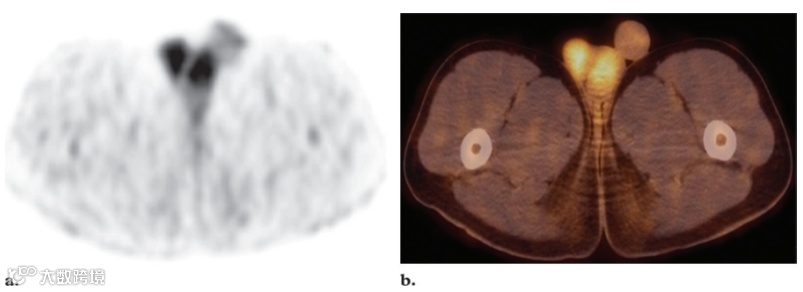

在男性中,睾丸摄取通常呈现对称和弥散的模式。强度通常为中等,并可能随着年龄的增长而降低(图11)。在女性中,子宫内膜通常表现出周期性变化的摄取,但在月经期间可以看到明显的摄取。有些研究者观察到绝经前女性生理活动增加的两个高峰:一个是在月经中期,另一个是在月经期。也有报道称,子宫肌瘤伴有明显的FDG摄取。正常情况下,卵巢中检测不到FDG摄取,但炎症过程、排卵卵巢和一些卵巢囊肿可能导致局部摄取增加,从而模仿淋巴结肿大(图12)。生理性黄体囊肿中也描述了局部摄取增加(图13)。生理性卵巢摄取的局部模式可能被误解为盆腔淋巴结肿大。PET/CT联合显像可以精确定位卵巢结构对FDG的摄取,从而更好地区分正常生理性摄取和病变。与患者讨论月经周期的阶段通常有助于区分生理性和恶性卵巢FDG摄取。

图11. 一名16岁男孩的睾丸生理性摄取,该男孩有左胫骨淋巴瘤病史。

轴位18F FDG PET 扫描 (a) 和融合PET/CT图像 (b) 显示睾丸中度和弥漫性摄取。CT未见异常。